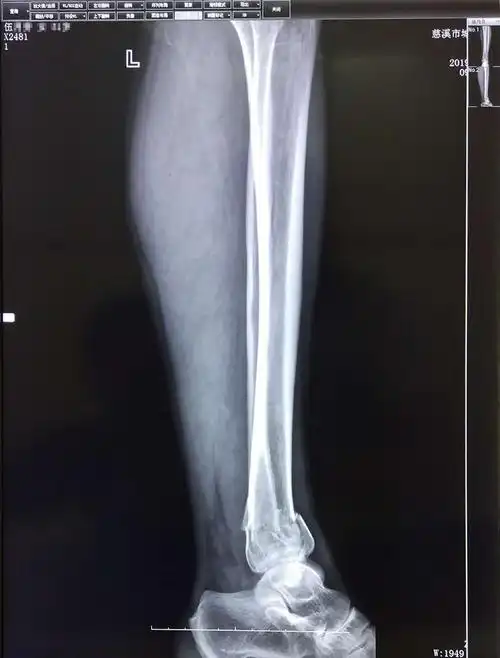

比较严重,不过经过检查,头脑没有什么问题,另外就是腿部有两处骨折

孙培权医师杏林妙手成功使下腿双骨折错位患者康复